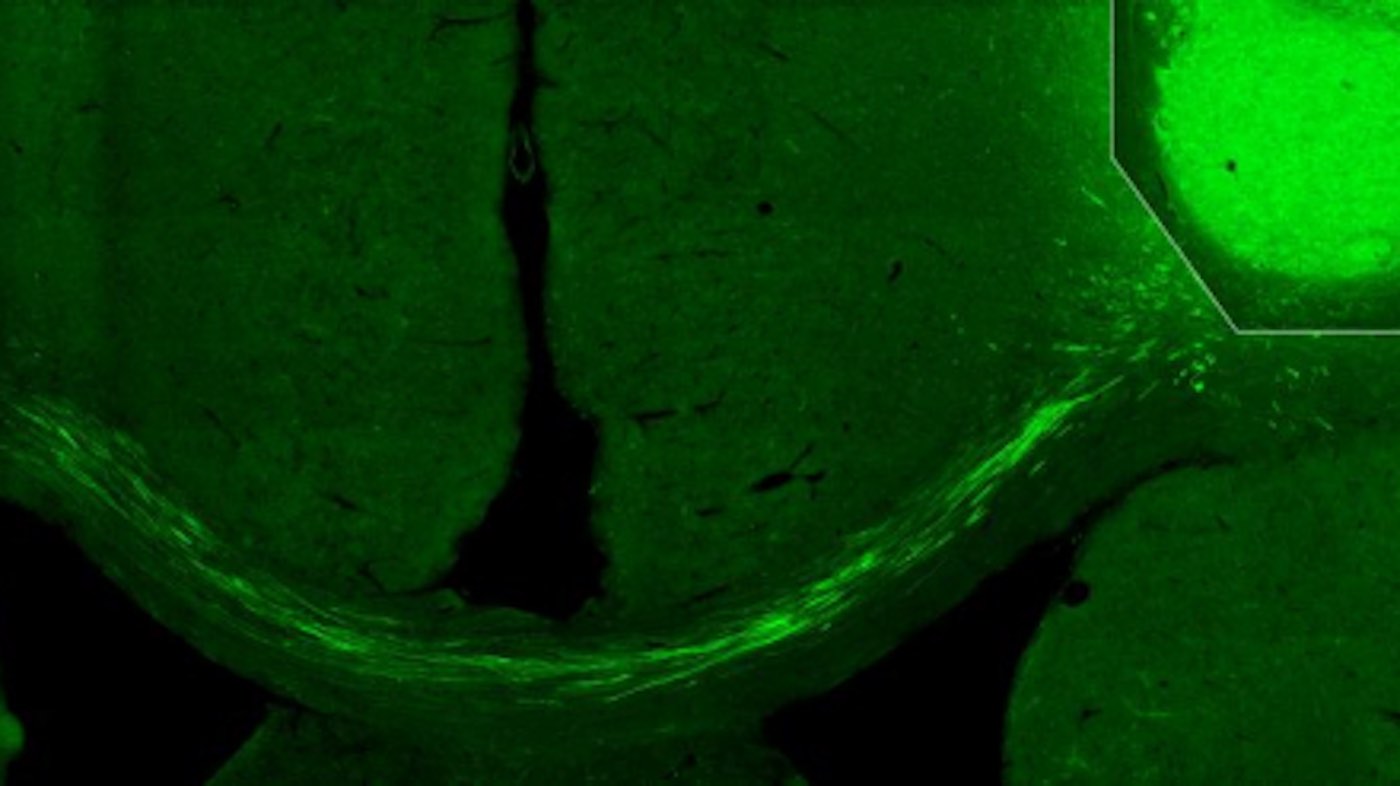

“We have used tracking techniques, electron microscopy and other methods, such as light to switch off activity in the transplanted cells, as a way to show that they really have connected correctly in the damaged nerve circuits. We have been able to see that the fibers from the transplanted cells have grown to the other side of the brain, the side where we did not transplant any cells, and created connections. No previous study has shown this,” says Kokaia, who—even though he and colleague senior professor Olle Lindvall have studied the brain for several decades—was surprised by the results.

The researchers have used human skin cells that have been reprogrammed in the laboratory to become nerve cells. They were then transplanted into the cerebral cortex of rats, in the part of the brain that is most often damaged after a stroke. Now the researchers will undertake further studies.

Photo by Lund University.